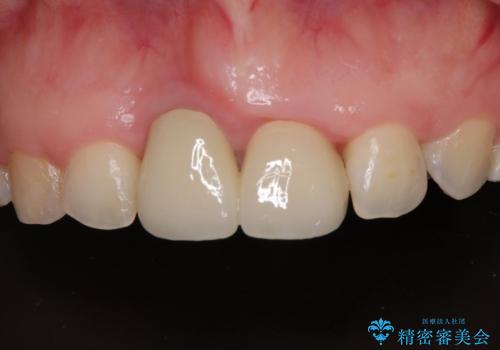

前歯のデコボコをワイヤー矯正で綺麗に 保険診療の前歯クラウンもセラミッククラウンで自然に

前歯のクラウンは変色が顕著なため、矯正治療後にオールセラミッククラウンによる補綴治療を行うこととしました。